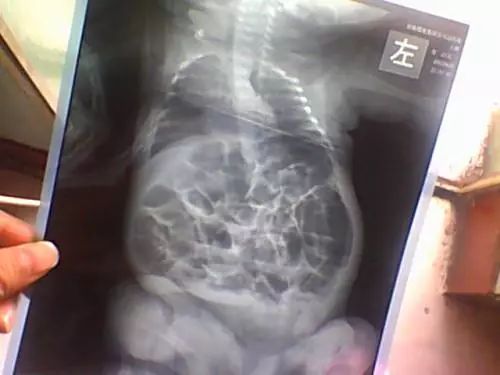

在肠绞痛发生时,宝宝的小脸会胀红、下肢蜷曲于肚子上,这种情形通常发作得很急,常见于下午及夜间,好发于3~6周新生儿。当然,妈妈不要过于紧张,等宝宝到了3个月大左右时,肠绞痛的发生率将大大降低。